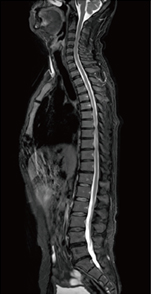

検査では,高速撮像法「IP-RAPID」とAI技術を活用して開発したノイズ除去技術「Synergy DLR」*を活用し,スキャン時間を抑えつつ画質を向上させており,遠隔読影を依頼している放射線科医や紹介検査の依頼元からも画質の良さが評判となっているという。Synergy DLRは強度(3段階)を変更可能なことから,川邊技師は,「読影医の要望に合わせて現在は基本的にlightを使用していますが,3Dはコントラストがついた方が見やすいためmediumを使用するなど,適宜使い分けています」と説明する。

陣内理事長は画質の向上が診療に与える影響について,「長寿化により糖尿病の患者さんを長期にわたり診療していると,がんも増加します。ECHELON Smart ZeroHeliumでは,MRCPの画質が大きく向上したと感じており,症状が現れにくい肝胆膵がんの早期診断の撮像に活用しています。前立腺がんもクリアな画像によりある程度の判断が可能と考えており,PSA値と総合的に判断して適切に紹介できるようになったと思います」と話す。